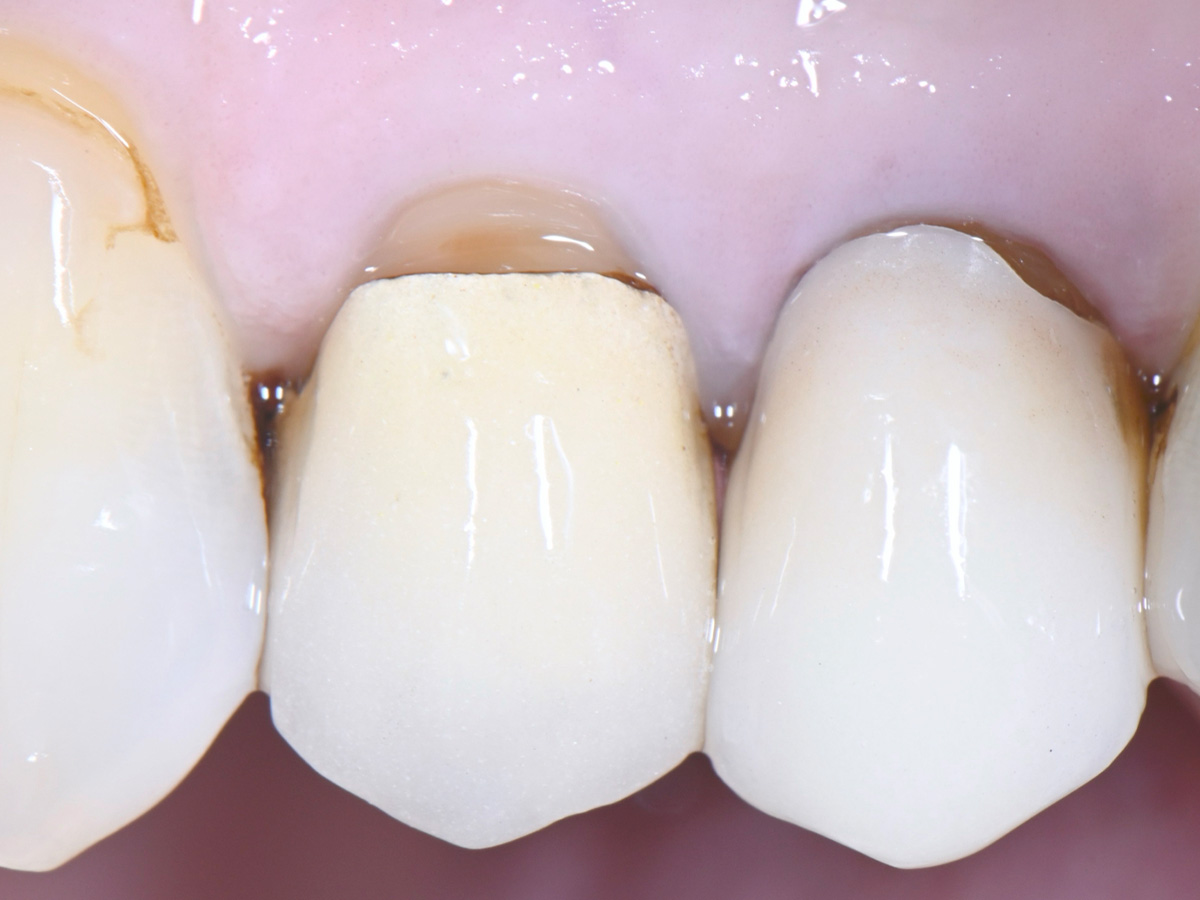

Abbildung 4

Vorsichtige Mobilisation der Wurzel mit einem modifizierten Desmotom